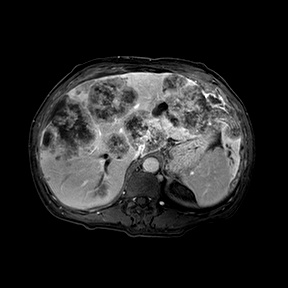

一位46岁男性患者,间歇性大便出血1年余,以为是痔疮,自行到药店买了痔疮药用,便血时断时续。后来体重明显下降,才在家人的建议下来温州医科大学附属第一医院结直肠肛门外科门诊就诊。问诊之后,医生给他做了直肠指检,基本明确是直肠癌而不是痔疮。接下来又安排他做了结肠镜检查和胸腹盆腔增强CT及直肠、肝脏MRI检查,结果发现是直肠癌伴肝转移,属于晚期。患者就这样因为自己的不重视,耽误了病情,非常可惜。

▲ 患者肝脏磁共振显示肝脏布满肿瘤